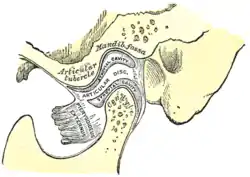

Anatomy and physiology

Temporomandibular joints

The temporomandibular joints are the dual articulation of the mandible with the skull. Each TMJ is classed as a "ginglymoarthrodial" joint since it is both a ginglymus (hinging joint) and an arthrodial (sliding) joint,[41] and involves the condylar process of the mandible below, and the articular fossa (or glenoid fossa) of the temporal bone above. Between these articular surfaces is the articular disc (or meniscus), which is a biconcave, transversely oval disc composed of dense fibrous connective tissue. Each TMJ is covered by a fibrous capsule. There are tight fibers connecting the mandible to the disc, and loose fibers which connect the disc to the temporal bone, meaning there are in effect 2 joint capsules, creating an upper joint space and a lower joint space, with the articular disc in between. The synovial membrane of the TMJ lines the inside of the fibrous capsule apart from the articular surfaces and the disc. This membrane secretes synovial fluid, which is both a lubricant to fill the joint spaces, and a means to convey nutrients to the tissues inside the joint. Behind the disc is loose vascular tissue termed the "bilaminar region" which serves as a posterior attachment for the disc and also fills with blood to fill the space created when the head of the condyle translates down the articular eminence.[42] Due to its concave shape, sometimes the articular disc is described as having an anterior band, intermediate zone and a posterior band.[43] When the mouth is opened, the initial movement of the mandibular condyle is rotational, and this involves mainly the lower joint space, and when the mouth is opened further, the movement of the condyle is translational, involving mainly the upper joint space.[44] This translation movement is achieved by the condylar head sliding down the articular eminence, which constitutes the front border of the articular fossa.[35] The function of the articular eminence is to limit the forwards movement of the condyle.[35] The ligament directly associated with the TMJ is the temporomandibular ligament, also termed the lateral ligament, which really is a thickening of the lateral aspect of the fibrous capsule.[35] The stylomandibular ligament and the sphenomandibular ligament are not directly associated with the joint capsule. Together, these ligaments act to restrict the extreme movements of the joint.[45]

Joint noises

Noises from the TMJs are a symptom of dysfunction of these joints. The sounds commonly produced by TMD are usually described as a "click" or a "pop" when a single sound is heard and as "crepitation" or "crepitus" when there are multiple, grating, rough sounds. Most joint sounds are due to internal derangement of the joint, which is instability or abnormal position of the articular disc.[46] Clicking often accompanies either jaw opening or closing, and usually occurs towards the end of the movement. The noise indicates that the articular disc has suddenly moved to and from a temporarily displaced position (disk displacement with reduction) to allow completion of a phase of movement of the mandible.[26][27] If the disc displaces and does not reduce (move back into position) this may be associated with locking. Clicking alone is not diagnostic of TMD since it is present in high proportion of the general population, mostly in people who have no pain.[26] Crepitus often indicates arthritic changes in the joint, and may occur at any time during mandibular movement, especially lateral movements.[26] Perforation of the disc may also cause crepitus.[35] Due to the proximity of the TMJ to the ear canal, joint noises are perceived to be much louder to the individual than to others. Often people with TMD are surprised that what sounds to them like very loud noises cannot be heard at all by others next to them. However, it is occasionally possible for loud joint noises to be easily heard by others in some cases and this can be a source of embarrassment e.g. when eating in company.